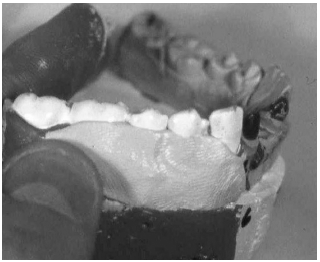

Temporizing splinting techniques available for use by emergency physicians include periodontal paste and self-cure composite. A commercially available form of periodontal paste, Coe-Pak, consists of a catalyst and a base that when mixed together form a sticky dressing that becomes firm after application. The splint performs best when applied to both the facial and oral surfaces of the teeth, but in cases where the tooth is only moderately luxated, oral surface application often is sufficient. It is most easily applied with wet hands or gloves to dry gingiva and enamel. (See Figure 9.) It is important to apply the dressing into the grooves between the teeth as well as to the adjacent teeth, and the patient should be reminded to eat a soft diet until follow-up can be arranged within 24-72 hours.

| Figure 9. Periodontal Paste |

|

Self-cure composite is another reasonable splinting option in the ED. Splinting composites used in the dentist's office require a curing light and etching acids to affix the bonding material, but self-cure composite requires neither and is easy to use. It is applied only to the enamel of the involved teeth and the adjacent firm teeth similarly to periodontal paste, but unlike periodontal paste, self-cure composite is not applied to the gingiva. (See Figure 10.) The disadvantage of self-cure composite is that it is rigid and not flexible and tends to pop off if the tooth is bumped in any way. Both periodontal paste and self-cure composites are easy for the dentist to remove during formal restoration.